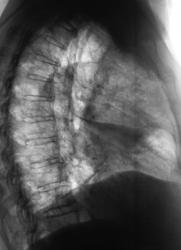

Томограммы в прямой проекции.

Добавлены линейные томограммы в прямой проекции.

Конечно налицо картина центрального рака правого главного бронха с разветвленным перибронхиальным ростом, лимфангитом справа, метастазами в лимфоузлы правого корня. Насчет параканкрозной пневмонии - неверное более справедлив термин - обструктивный пневмонит... В правом легком множественные ячеистые структуры - поликистоз.

А мне что-то видится осумкованный экссудат в горизонтальной м/долевой щели, придавливающий сверху среднюю долю. Кажется есть и диафрагмальный экссудат. Обструкции крупного бронха не вижу, правда на этих томограммах не определяется Br2. Явная патология верхней доли без уменьшения её объёма. Бронхопульмональные лимфоузлы впечатляют, а вот медиастинальные что-то не очень. Ну допустим перибронхиальный рост…, но вдоль каких бронхов?